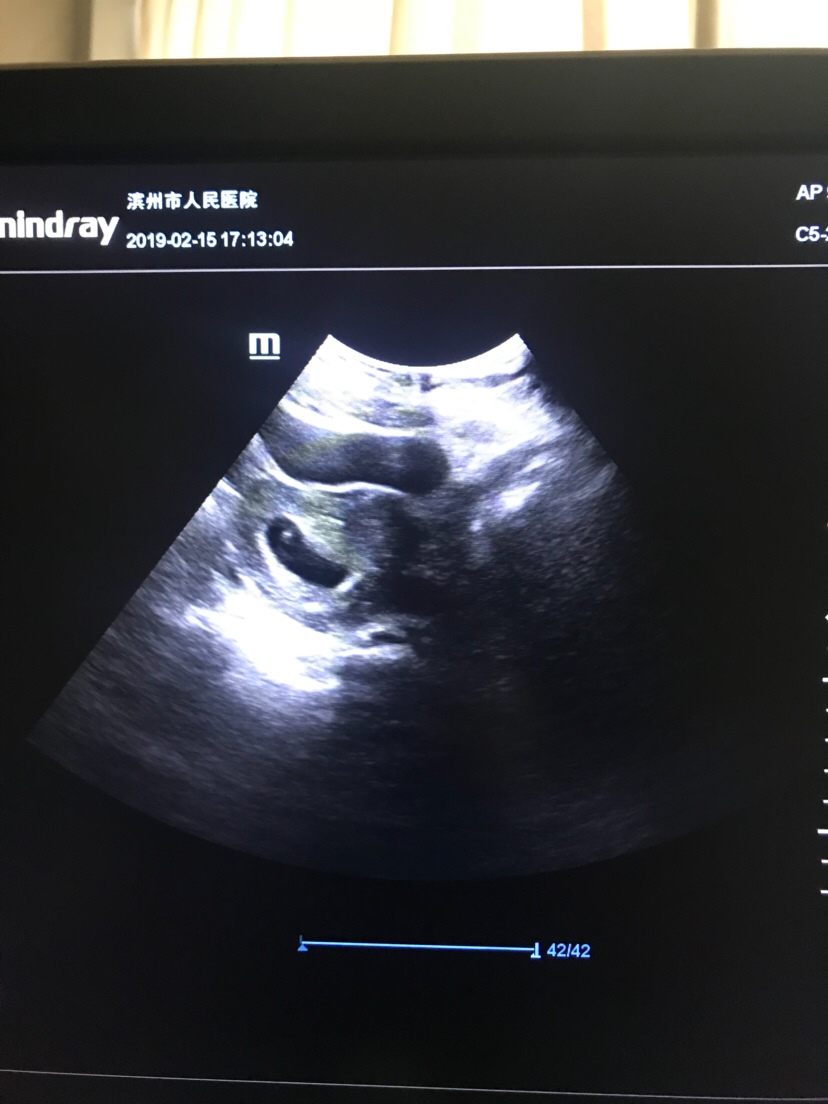

HYGJCQ70[帖主]:六周两天

我今天去照都有了 但是有宫腔积液 医生还开了保胎药 吓死了